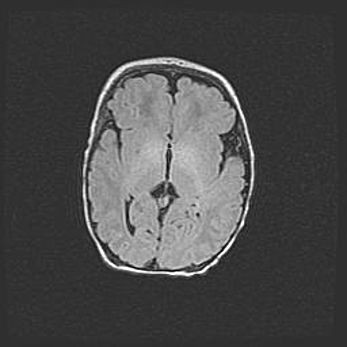

Лейкомаляция с кистозно-глиозной дегенерацией головного мозга.

Возраст: 2 месяца 25 дней

Вес: 6400 г

Окружность головы: 40 см

Срок гестации: 41 неделя

Лейкомаляцию относят к ишемически-гипоксическим повреждениям головного мозга, диагностируемым у новорожденных. При лейкомаляции в головном мозге обнаруживают очаги некроза, возникшие после тяжелой гипоксии и нарушения кровотока. В процессе морфогенеза очаги проходят три стадии: 1) развития некроза, 2) резорбции и 3) формирования глиозного рубца или кисты. Перивентрикулярная лейкомаляция (ПЛ) встречается примерно в 12% случаев среди новорожденных, обычно – у недоношенных детей, причем, частота ее зависит от массы, с которой младенец появился на свет. Наибольшее число малышей страдает лейкомаляцией, если масса при рождении 1500-2500 г.